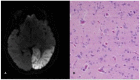

In the last ten years, the knowledge of the genetic basis of mitochondrial diseases has significantly advanced. However, the vast phenotypic variability linked to mitochondrial disorders and the peculiar characteristics of their genetics make mitochondrial disorders a complex group of disorders. Although specific genetic alterations have been associated with some syndromic presentations, the genotype-phenotype relationship in mitochondrial disorders is complex (a single mutation can cause several clinical syndromes, while different genetic alterations can cause similar phenotypes). This review will revisit the most common syndromic pictures of mitochondrial disorders, from a clinical rather than a molecular perspective. We believe that the new phenotype definitions implemented by recent large multicenter studies, and revised here, may contribute to a more homogeneous patient categorization, which will be useful in future studies on natural history and clinical trials.